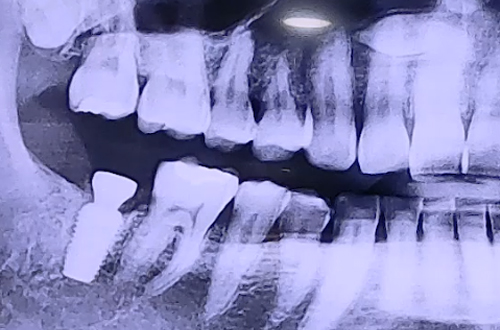

BEFORE

충치 치료를 진행한 치아에서 음식을 씹을 때마다 지속적으로 불편감을 느끼던 도중

어느 순간 극심한 통증을 느끼고 내원해 주셨던 환자분의 사례입니다.

치아 상태를 정밀검사 해본 결과, 골드인레이가 진행된 오른쪽 어금니에서

인레이 뒤쪽으로 치아가 쪼개져 금이 생겨있는 것이 발견되었는데요.

치아가 쪼개지면서 신경에도 통증을 유발해 아프셨던 것입니다.